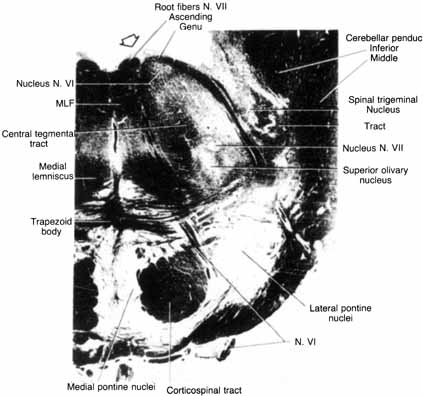

PONS

The facial motor nucleus contains about 7,000 motor nuclei 8 and is located in the ventrolateral angle of the lower pontine tegmentum (see Fig. 1). The facial nucleus can be divided into four separate cell groups that supply specific muscle groups: (1) dorsomedial (auricular and occipital muscles), (2) intermediate (frontalis, corrugator, and orbicularis oculi muscles), (3) ventromedial (platysma), and (4) lateral (buccinator and buccolabial).9 The motor axons exit the nucleus dorsally, loop around the abducens (VI) nucleus, and form the facial genu before emerging from the lateral aspect of the pons. The superior salivatory nucleus, which is located just rostral to the facial motor nucleus, is the origin of the parasympathetic fibers that supply the sublingual, submandibular, and lacrimal glands. These salivary and lacrimal fibers join the facial nerve as the nervus intermedius in the cerebellopontine angle.

Because the facial nucleus is located ventromedial to the cochlear nuclei and the spinal tract and nucleus of the trigeminal nerve, a lesion of the lateral pons may result in ipsilateral facial paresis, ipsilateral facial analgesia, ipsilateral Horner's syndrome, and ipsilateral deafness (Foville's syndrome). If the lesion extends further dorsally, an ipsilateral gaze paresis would result from involvement of the sixth nerve nucleus. The combination of a unilateral sixth nerve palsy, an ipsilateral seventh nerve palsy, and a contralateral hemiparesis is known as the Millard–Gubler syndrome. Intrinsic lesions of the brain stem are usually the result of infarction, hemorrhage, tumor, or demyelination.